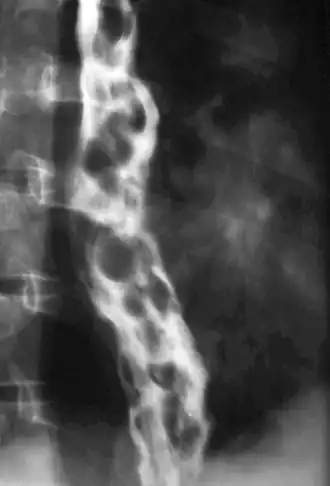

Oesofagusvarices

Oesofagusvarices of slokdarm-spataderen zijn verwijde bloedvaten in de wand van de slokdarm. Ze treden vaak op als de lever niet meer in staat is het bloed uit de poortader van de darmen te verwerken. Dit zoekt zich dan een weg langs de lever, en vindt die in een netwerk van aderen die rond de slokdarm lopen. Deze raken dan verwijd.